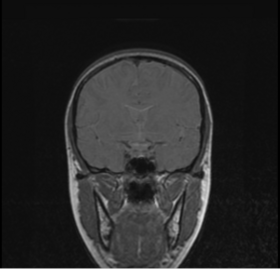

BRAINSMush uses the Maximize Uniformity Summation Heuristic(MUSH) optimizer, as developed at the University of Iowa, to extract the brain and surface CSF from a multi-modal imaging study. It forms a linear combination of multi-modal MR imaging data to make the signal intensity within the brain as uniform as possible. This resulting image is then thresholded to obtain the brain and surface CSF region.

The image is thresholded by the mean signal intensity plus-or-minus five standard deviations.

This method was applied to a sample of 20 MR brain scans and its results were compared to those obtained by 3dSkullStrip, 3dIntracranial, BET and BET2. The average Jaccard metrics for the twenty subjects was 0.66(BET), 0.61(BET2), 0.88(3dIntracranial), 0.91(3dSkullStrip) and 0.94(MUSH).